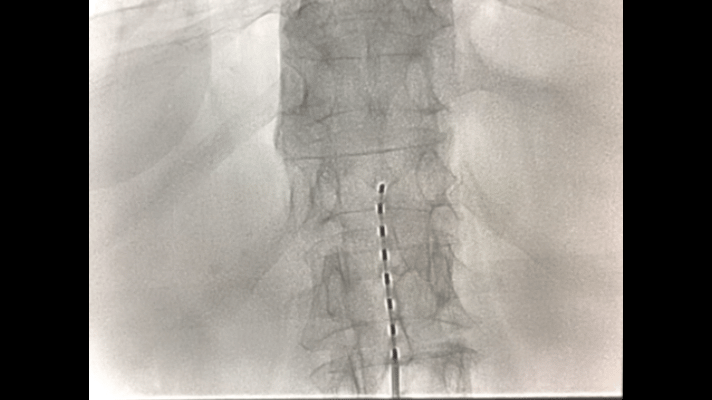

▲置入椎管内的电极

蓝志坚解释,人身体部位的疼痛要通过脊髓传到大脑的痛觉感中枢,人感觉到痛是因为大脑的痛觉感中枢接收到了脊髓传导的疼痛信号,那么把疼痛信号阻截在脊髓传导的半路上,人自然疼痛感减轻或缓解了。脊髓电刺激疗法是将一根直径只有1.4毫米的8节电极放于椎管内,用脉冲电流抑制脊髓神经的痛觉信号传导,从而缓解慢性顽固性疼痛,同时也可以对损坏的神经进行修复。